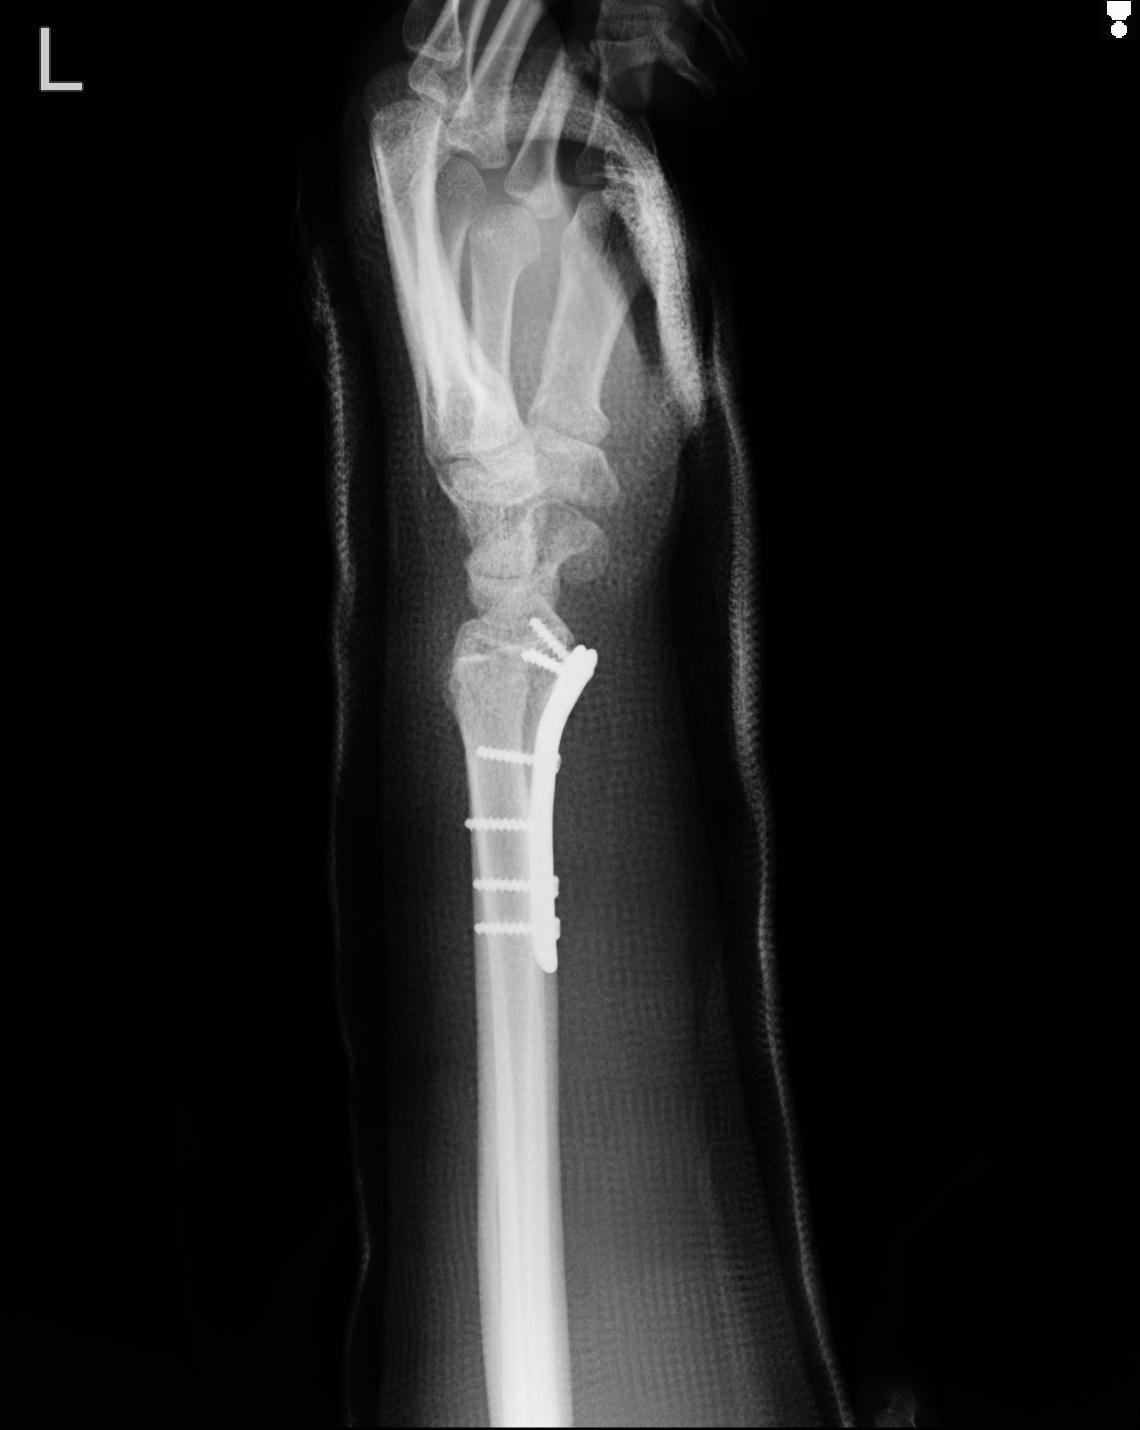

102766 1/5 1/12 左手関節 4R 28歳男性 左橈骨遠位端